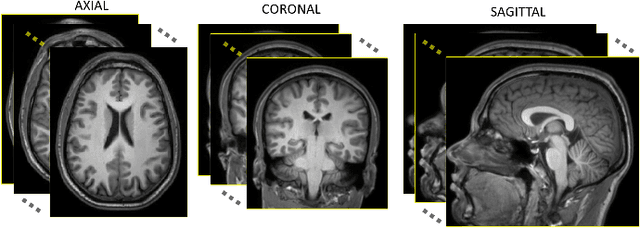

Abstract:Medical image segmentation is an increasingly popular area of research in medical imaging processing and analysis. However, many researchers who are new to the field struggle with basic concepts. This tutorial paper aims to provide an overview of the fundamental concepts of medical imaging, with a focus on Magnetic Resonance and Computerized Tomography. We will also discuss deep learning algorithms, tools, and frameworks used for segmentation tasks, and suggest best practices for method development and image analysis. Our tutorial includes sample tasks using public data, and accompanying code is available on GitHub (https://github.com/MICLab-Unicamp/Medical-ImagingTutorial). By sharing our insights gained from years of experience in the field and learning from relevant literature, we hope to assist researchers in overcoming the initial challenges they may encounter in this exciting and important area of research.

Abstract:The 2020 Multi-channel Magnetic Resonance Reconstruction (MC-MRRec) Challenge had two primary goals: 1) compare different MR image reconstruction models on a large dataset and 2) assess the generalizability of these models to datasets acquired with a different number of receiver coils (i.e., multiple channels). The challenge had two tracks: Track 01 focused on assessing models trained and tested with 12-channel data. Track 02 focused on assessing models trained with 12-channel data and tested on both 12-channel and 32-channel data. While the challenge is ongoing, here we describe the first edition of the challenge and summarise submissions received prior to 5 September 2020. Track 01 had five baseline models and received four independent submissions. Track 02 had two baseline models and received two independent submissions. This manuscript provides relevant comparative information on the current state-of-the-art of MR reconstruction and highlights the challenges of obtaining generalizable models that are required prior to clinical adoption. Both challenge tracks remain open and will provide an objective performance assessment for future submissions. Subsequent editions of the challenge are proposed to investigate new concepts and strategies, such as the integration of potentially available longitudinal information during the MR reconstruction process. An outline of the proposed second edition of the challenge is presented in this manuscript.